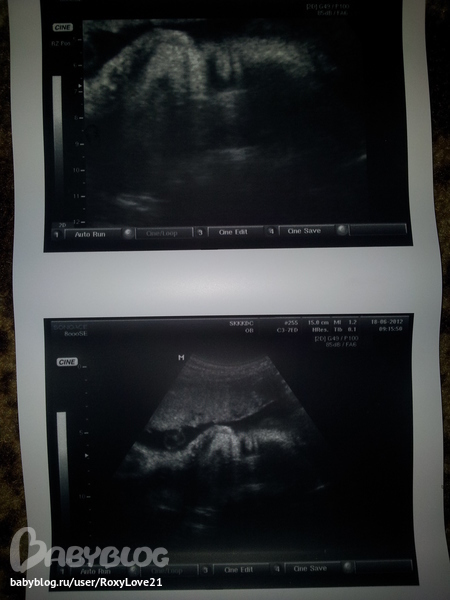

Сегодня были на долгожданном узи с мужем!!!

Слава Богу, все хорошо. У нас 30 неделек,ребенок соответствует всем параметрам.Лежит головкой вниз,весим мы 1550г . Подтвердили,что в животике у мамы сидит мальчишка)))

Жаль мне ничего не видно было,только на снимках увидела свою ляльку и то получилось только запечатлить личико,так как он сильно крутился и не давал сделать хороший снимок.Зато мы ладошкой щечку подпираем)))

Вот решила поделиться увиденным с вами,не знаю только удасться ли вам разглядеть что-нибудь...Вот такие мы)))